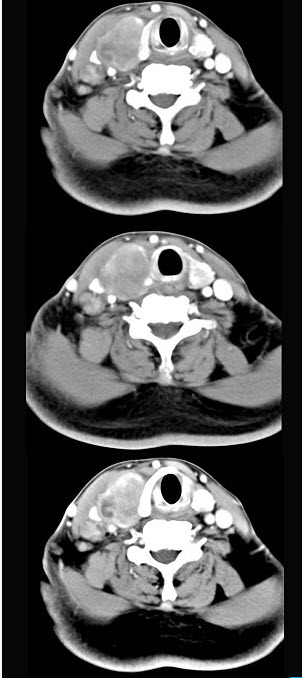

- 多项选择题女性,54岁,右侧颈部肿大近1年,近来病人有声嘶、吞咽困难,CT扫描如图,请选择正确的描述和答案()。

A、右侧甲状腺肿大,密度减低

B、增强扫描示甲状腺呈不规则强化团块影,其内有低密度区,病灶境界不清

C、右侧颈内静脉增粗,其内可见不规则充盈缺损区

D、考虑甲状腺癌

E、右侧颈内静脉瘤栓形成

- A,B,C,D,E